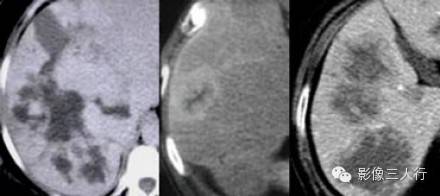

许多病变都显示逐步填充。血管瘤的逐步填充密度必须与血池密度一致。许多恶性转移瘤对比强化也从周边向瘤内扩散,通常中心不填充。胆管癌的逐步填充是因为中心纤维强化缓慢,只有在延迟期时才增强。如果要做出血管瘤的诊断就要与其他时相结合,观察其密度是否与血池一致。

血管瘤(左)、胆管癌(中) 和转移瘤(右图)的逐步填充。